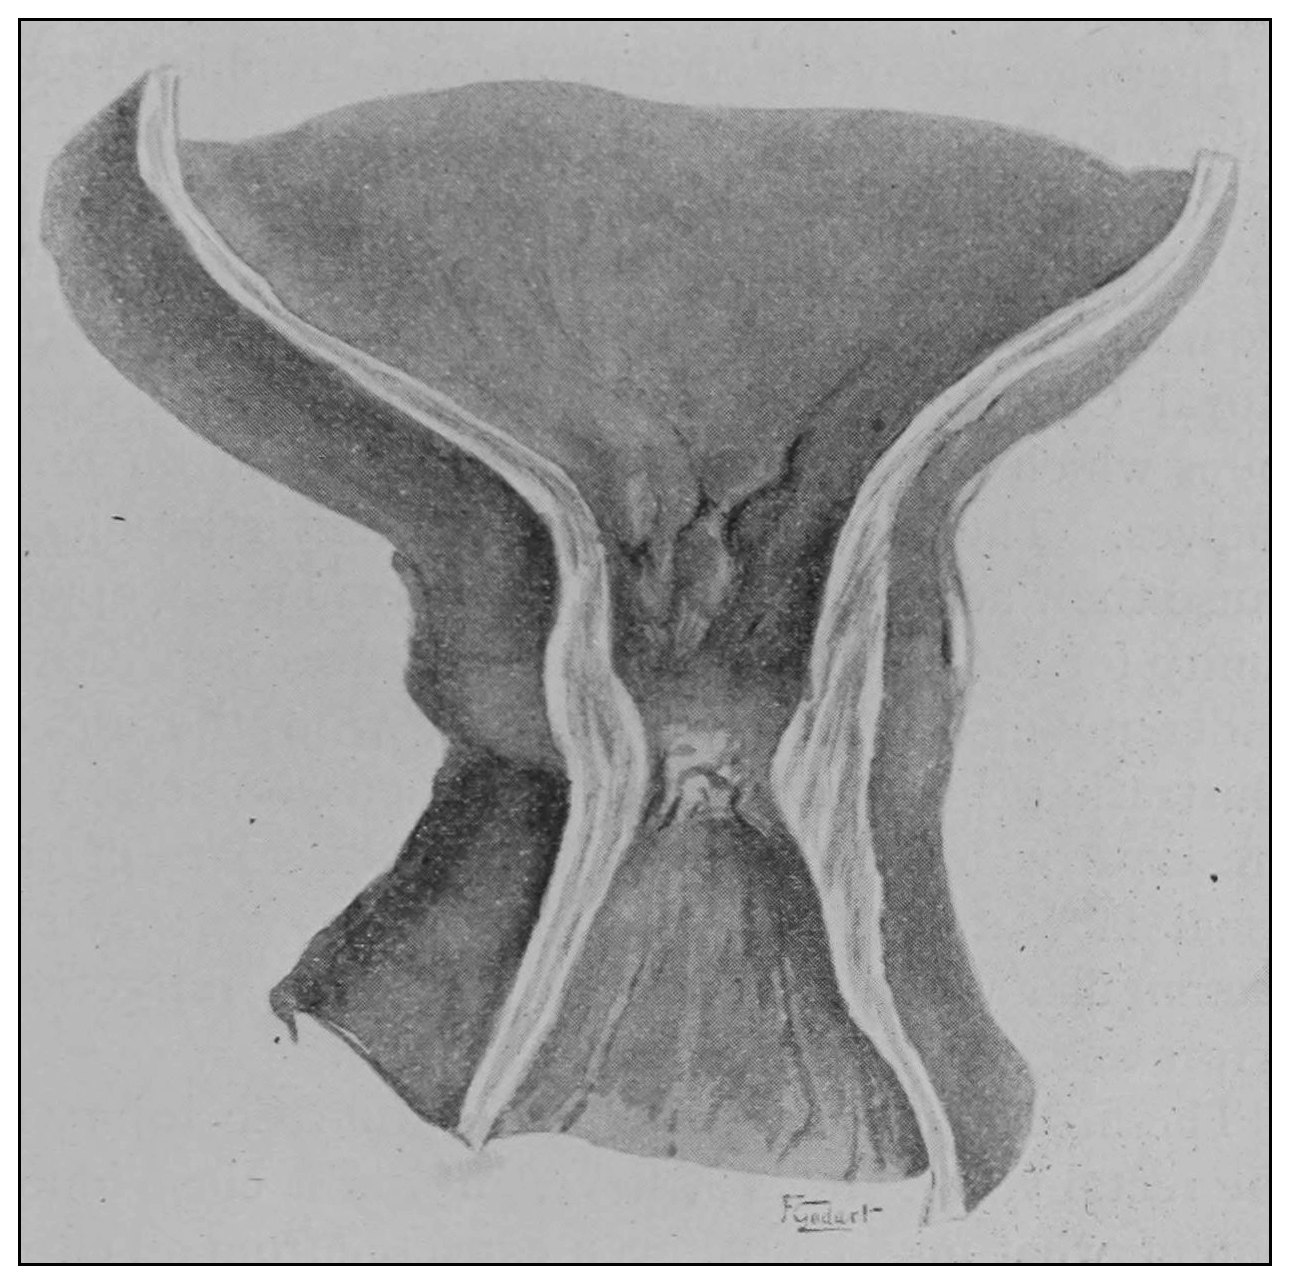

Fig. 19.—Drawing of specimen No. 281 in the Anatomical Museum of the Royal College of Surgeons, London. The dissection was made by Mr. William Pearson. The drawing shows in the lower part of the field the coccyx, in the upper part of the field the pubes.

Fig. 20.—Drawing of specimen No. 284 in the Anatomical Museum of the Royal College of Surgeons, London. The dissection was made by Mr. William Pearson. The drawing shows in the lower part of the field behind the rectum the coccyx, in the upper part of the field the pubes.